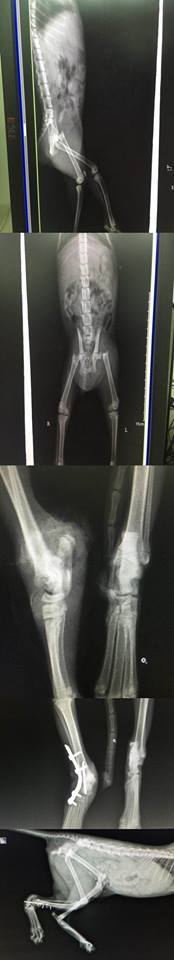

主題: 被丟包的斷腿小虎斑 申請者姓名: 許桂菱 花色: 申請日期: 2016-10-22 23:59:56 申請者部落格: 申請者臉書網址: 所在縣市/合作醫院: 彰化縣/成愛動物醫院 治療費用: 30000元 需求人數: 32人 已結案 (2024-06-01 13:34:34) 報名人員: Lichen Liao x2(已付款)、Caitlin、薇薇安(已付款)、王琇盈(已付款)、Millie Liao(已付款)、陳昱先 x4、陳昱先 x2(已付款)、Erin Lin(已付款)、Wester Wei(已付款)、李夢話 x2(已付款)、Iris Hsu、嘟嘟白白(已付款)、Chihai Chang x2(已付款)、點點(已付款)、chucl(已付款)、林曉林 x2(已付款)、Emily(已付款)、吉兒(已付款)、菲小比(已付款)、Shane(已付款)、Polly Ma(已付款)、Caitlin(已付款)、May x2(已付款)、Jing Yi Hsu(已付款)、Yi-Ling Yao(已付款)、Tiffany Shen(已付款)、夏夏發發 x3(已付款)、 候補人員: 動物病情說明: 7/1晚間才剛結束第一個餵養區誘捕母街貓送醫後,前往第二個餵養區發現一個被倒放紙箱,一陣寒意以為可能是貓大體,結果翻正一看是一隻無法行走的小貓,雖然受傷但也是哈氣出爪,於是只能用大塑膠袋套住紙箱趕緊送醫,檢查有幾處傷口,但不是非常嚴重的,經過X光片發現左腳大腿骨斷掉,腸薦骨有些移位需觀察,右小腿也腫脹!

7/1晚間照X光片,確認左腳股骨斷掉,腸薦骨移位,有多處小傷口,右後小腿有腫脹,先施打一般消炎針!

7/11 清創包紮時發現右後腿的跟骨斷掉,評估後將與腸薦骨手術一起進行,以免增加麻醉風險,另外右前掌也掉了一塊肉!

7/12 進行腸薦骨及跟骨手術,醫生說跟骨的部分沒什麼肉,擔心如果血液供給不足或感染嚴重,就必需要截肢到膝蓋處,每天早晚需施打抗生素!

7/14~7/19 每日清創包紮及抗生素治療,傷口部份還不錯,但跟骨的螺絲每日檢查都會鬆掉!小母貓兇悍隨時警戒,但食慾都不錯,排便也正常,醫生擔心跟骨部份恢復時間會拉長!

7/20~7/25 右後腿每日清創包紮,但跟骨最下方第四顆螺絲因小貓骨頭小無法鎖緊,醫生評估就不再上螺絲固定,傷口周圍已漸漸在長肉,持續控制傷口感染,醫生說需等肉長好包覆完全,恢復穩定後,還需將接片跟其他3顆螺絲移除!

8/10~8/16 跟骨傷口每日清創包紮,持續長肉且無感染,8/15再照X光片,跟骨接合度尚未完全,預估需再一個月才能將固定之鎖板鐵片拆除!

9/08 再照x光片,先將骨板取出,骨內釘的部分要再2星期左右,等掌骨上面再長好ㄧ點才拆,最後這次取釘會一起做結育手術!